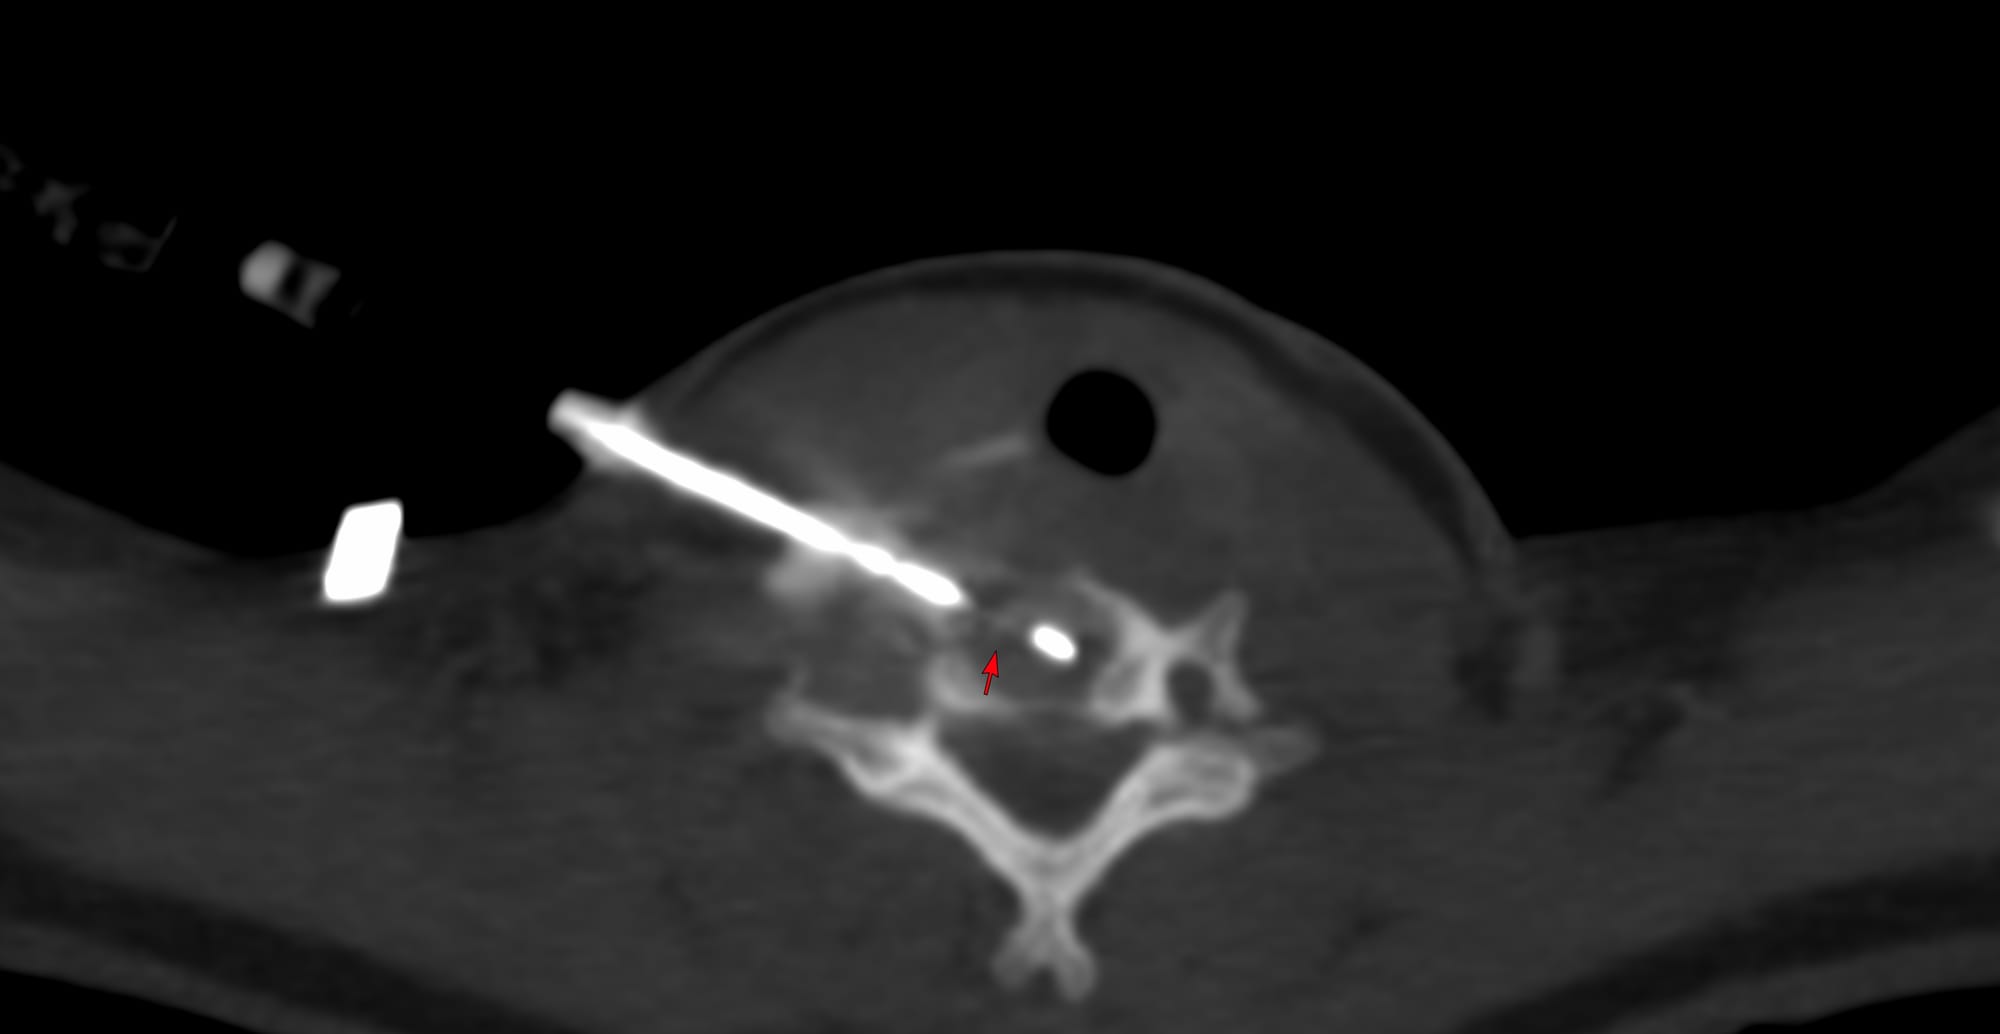

Case of the Day 100 - 2025 09 10 - T2 Dark Thoracic Spinal Vertebral Lesion - Transpedicular Biopsy

Bhavin Jankharia - 14 September 2025